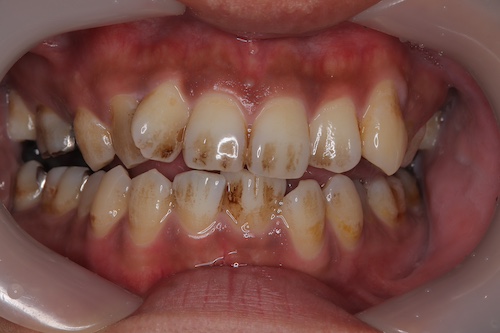

バコ1日20本吸う20代男性クリーニングでステインを除去

20代男性喫煙6年 一日20本、クリーニング希望 ステイン除去希望

1回のクリーニングでのステイン除去、ビフォーアフター写真

一回でここまでステイン取れて嬉しそうにされていた。